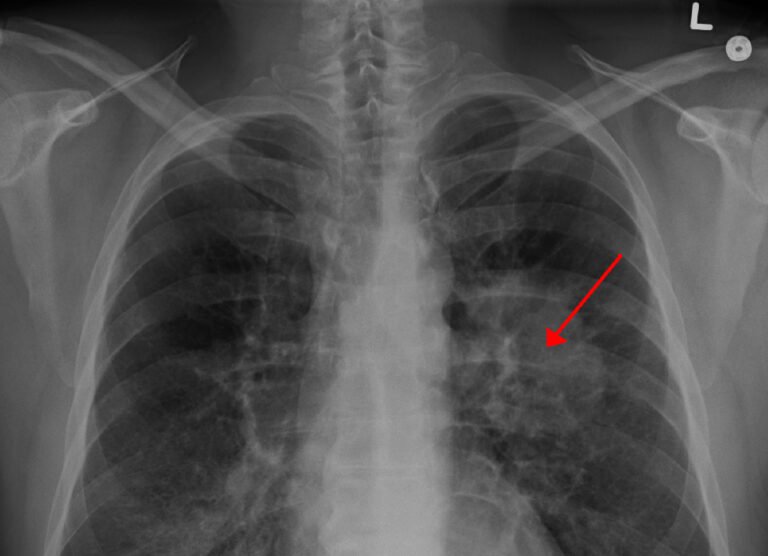

Aunque cada vez hay menos fumadores en el mundo, el cáncer de pulmón sigue siendo una de...